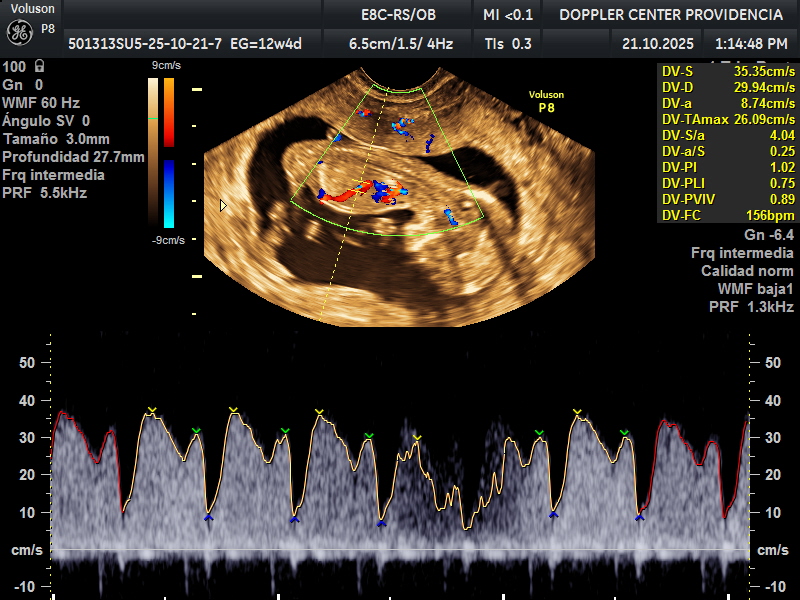

Es una técnica especializada de ultrasonido que utiliza el efecto Doppler para evaluar el flujo sanguíneo en el sistema circulatorio del feto y la madre durante el embarazo.

Se usa principalmente para evaluar el flujo sanguíneo en la placenta, el cordón umbilical y los vasos sanguíneos de la madre y el feto. Esto proporciona información valiosa sobre la salud del embarazo y la circulación fetal.

• Eco Doppler 11-14 semanas